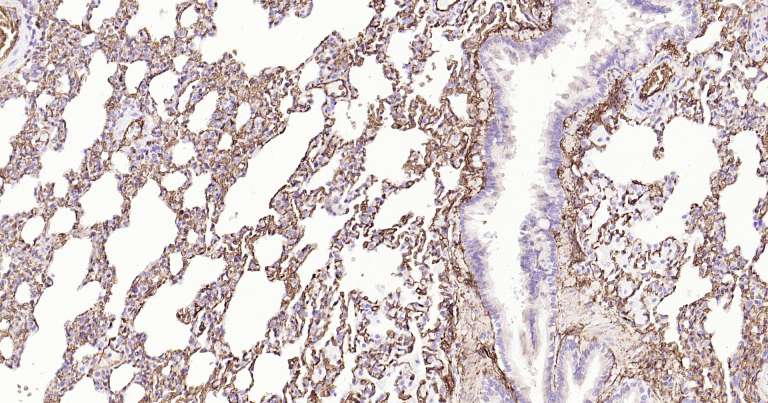

Immunohistochemical analysis of paraffin embedded rat kidney tissue slide using IHC0255R (Rat AQP1 IHC Kit).

Immunohistochemical analysis of paraffin embedded rat lung tissue slide using IHC0255R (Rat AQP1 IHC Kit).